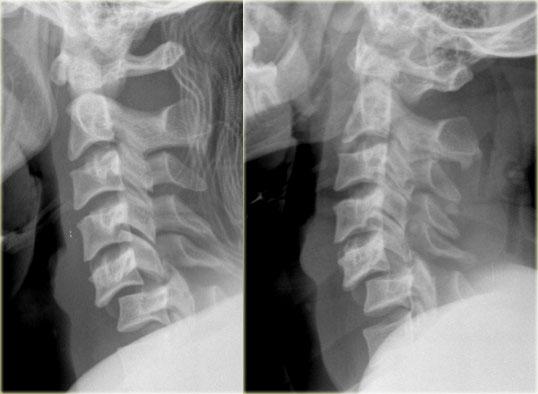

Bên trái là hình ảnh của một nam giới 20 tuổi bị tai nạn xe cơ giới lật xe.

Các dấu hiệu trên X-quang bao gồm:

- Tăng gấp tại mức C4-C5 với khoang gian gai rộng ra

- Trật khớp tại mức C4-C5 với khoảng trượt khoảng 25% (tức là di lệch ra trước 25% đường kính trước-sau của thân đốt sống)

- Mất thẳng hàng của các mỏm gai trên phim thẳng (AP), chỉ có thể xảy ra do chấn thương xoay. Mỏm gai bị tổn thương hướng về phía bên bị tổn thương

- Do xoay, các mỏm gai của C4 và C5 trông ngắn hơn trên phim nghiêng

CT xác nhận trật khớp một bên.

Khớp mặt bên đối diện chỉ bị giãn cách.